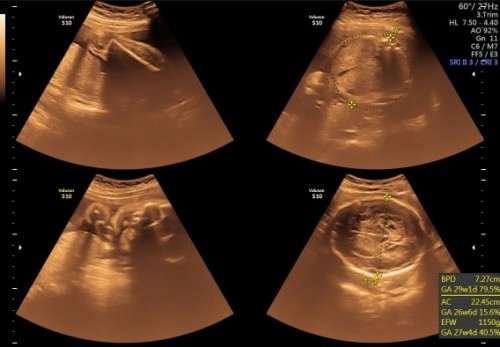

halo bunda2 semua semalam saya pergi usg kehamilanku 7 bulan nah disitu sayaa sama suamiku mau lihat dedenya cewe atau cowok , tpi eh si dede gak mau buka pahanya !!kata dokter si gitu tpi setelah dilihat terus menerus , kata dokter 70% cewe .. karena kalaau anaknya cowok gampang banget dan cepat ditau menurut bunda2 semua apakah itu akurat atau tidak , apakah bisa berubah lagi jk nyaa 😔 MAKASIH🤗#seriusnanya